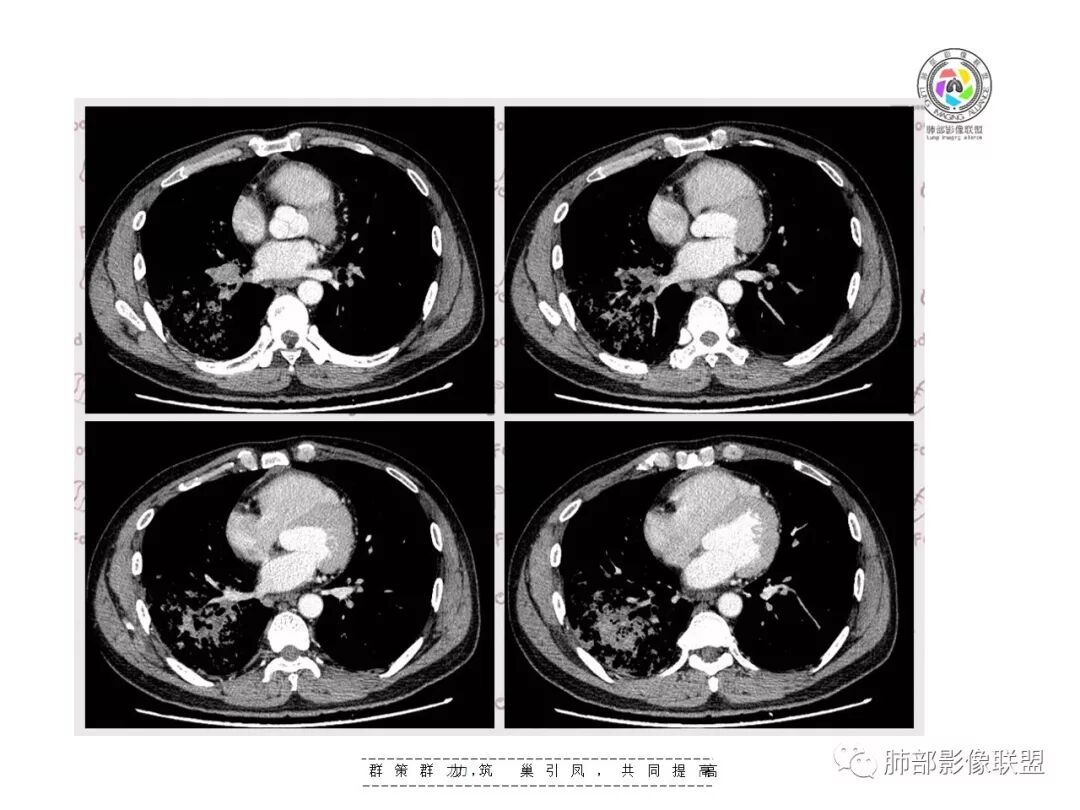

王秀仙东宁市第二人民医院影像科:晨读:右肺下叶实变及磨玻璃影,边缘有收缩有膨隆,部分支气管进入扭曲扩张,磨玻璃影边缘清晰,实变影明显强化,内可见血管造影征,纵膈及肺门淋巴结肿大并强化,考虑粘液腺癌。

登封市三康医院(刘权威):右下肺肺不张,磨玻璃影,边缘清楚,空气支气管征,增强有强化,纵膈及右肺门淋巴结肿大并强化,考虑恶性肿瘤,粘液腺癌可能。

但是问题来了:淋巴结

右肺门区淋巴结增大,融合,密度均匀,均匀强化

符合这个特点的:结核?淋巴瘤?转移瘤?

淋巴结我觉得目前的特点:淋巴瘤?结核?

复查胸部CT视频显示肺部病灶明显吸收,淋巴结较前缩小。

患者在本院做了支气管镜,报告是有新生物,取了活检就转院了。病理结果是后来出来的。去肿瘤医院再做支气管镜,病理还是炎症。抗炎治疗(电话追问患者家属,具体不详)一个月后复查,右下肺病变基本吸收,肺门肿块明显变小;纵隔淋巴结基本都没了或者明显变小了

我一直以为是二元的,我觉得特别淋巴结里面又有钙化灶,我的想法肺部就是炎性病变,因为很典型的分布符合气道来源炎性病变,但是淋巴结是独立出来的,里面有钙化灶怀疑结核可能。